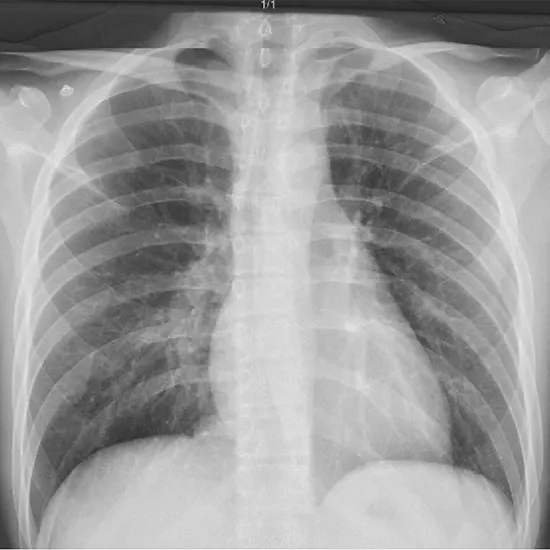

X-Ray Chest Right Oblique View

Book X-Ray Chest Right Oblique View Appointment Online Near me at the best price in Delhi/NCR from Ganesh Diagnostic. NABL & NABH Accredited Diagnostic centre and Pathology lab in Delhi offering a wide range of Radiology & Pathology tests. Get Free Ambulance & Free Home Sample collection. 24X7 Hour Open. Call Now at 011-47-444-444 to Book your X-Ray Chest Right Oblique View at 50% Discount.

The oblique view of the chest is a unique projection used to look at the back of the ribs, the esophagus, lesions that are visible in the PA view but not in the lateral view, and the origin of a lesion. This test looks at the lungs and the area between the lungs and the heart.